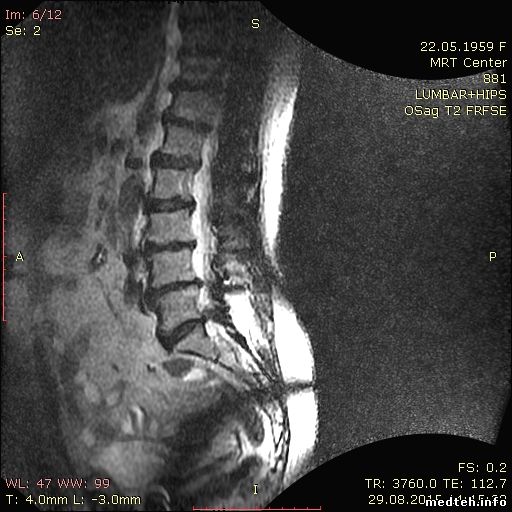

МРТ GE Signa Profile 0,2T 2007г выпуска. При сканировании грудного или поясничного отдела позвоночника на катушках BODY и CTL, только на последовательности Т2 Sag, появляются помехи на изображении в виде дуги.

Может кто подскажет, с чем это может быть связано? Может кто сталкивался с такой проблемой.

я не имел дела с GE, но такая "дуга" очень похожа нарушение работы одной из градиентных катушек, я бы даже сказал, что это Z-гадиент

slaval, это у вас, скорее всего, просто край катушки или проблемы с однородностью B1.

Проверьте, что у вас исследуемая область находится в центре поля сканирования - уж очень крутая дисторсия на картинках.

Elya, посмотрите на то, как выглядит край приемной зоны на CP Extremity. Очень похоже. Градиенты тут вообще не при делах.

извиняюсь, попутал.. неполадки с градиентами глобально влияют на картинку, а здесь точно что-то с областью сканирования, наложение срезов получается